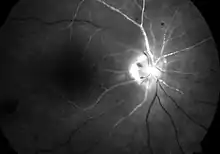

| Cherry red spot in a person with central retinal artery occlusion | |

[[File:|thumb|390x390px||alt=]] Central retinal artery occlusion is characterized by painless, acute vision loss in one eye.[5] Upon fundoscopic exam, one would expect to find: cherry-red spot (90%) (a morphologic description in which the normally red background of the choroid is sharply outlined by the swollen opaque retina in the central retina), retinal opacity in the posterior pole (58%), pallor (39%), retinal arterial attenuation (32%), and optic disk edema (22%).[5] During later stages of onset, one may also find plaques, emboli, and optic atrophy.[5]

Cherry-red spot with retinal pallor typical of central retinal artery occlusion